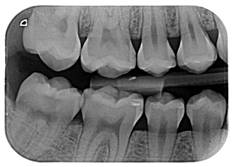

3.5. Clinical Scenario #5

In this scenario, the participants were asked to select the most adequate treatment option for the treatment of the carious lesions present in teeth 1.3, 1.2, 1.1, 2.1, 2.2, and 2.3. The most prevalent answer for teeth 1.3, 1.1, 2.1, and 2.3 (94.2%) was “remineralization” (clinical scenario 5a), which was the correct answer. For tooth 1.2 (clinical scenario 5b), the most prevalent answer was “root canal treatment” (51.2%), followed by “restoration with resin composite” (22%). For tooth 2.2 (clinical scenario 5c), the most popular option was “restoration with resin composite” (85.4%), followed by “remineralization” (22%). The correct answer for teeth 1.2 and 2.2 was “restoration with resin composite” (Figure 1).

The majority of students coincided with the available protocols for approaching active carious lesions limited to enamel (clinical scenario 5a). However, when lesions extended to dentin (clinical scenarios 5b and c), the therapeutic alternatives were more discordant. Specifically, for the treatment of tooth 1.2, in which the extension of the carious lesion surpassed the external third of the dentin, 51.2% of the students proposed a root canal treatment, which is considered as an overtreatment in this case [35].